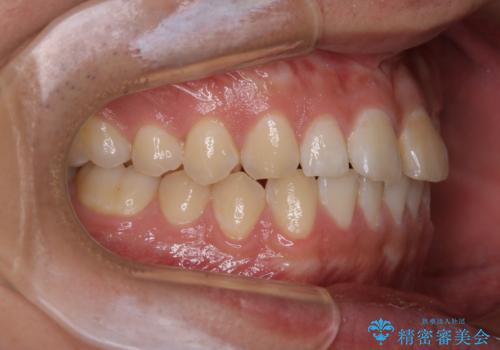

- 矯正治療を考えていて、歯科医院が久しぶりのためまずはクリーニングしたいとのことでした。PMTC60分コースを行いました。

今後、矯正を考えている場合は、まず現状の口腔内をチェックし、虫歯や歯周病などを早期に発見し進行を防ぐことが大切です。